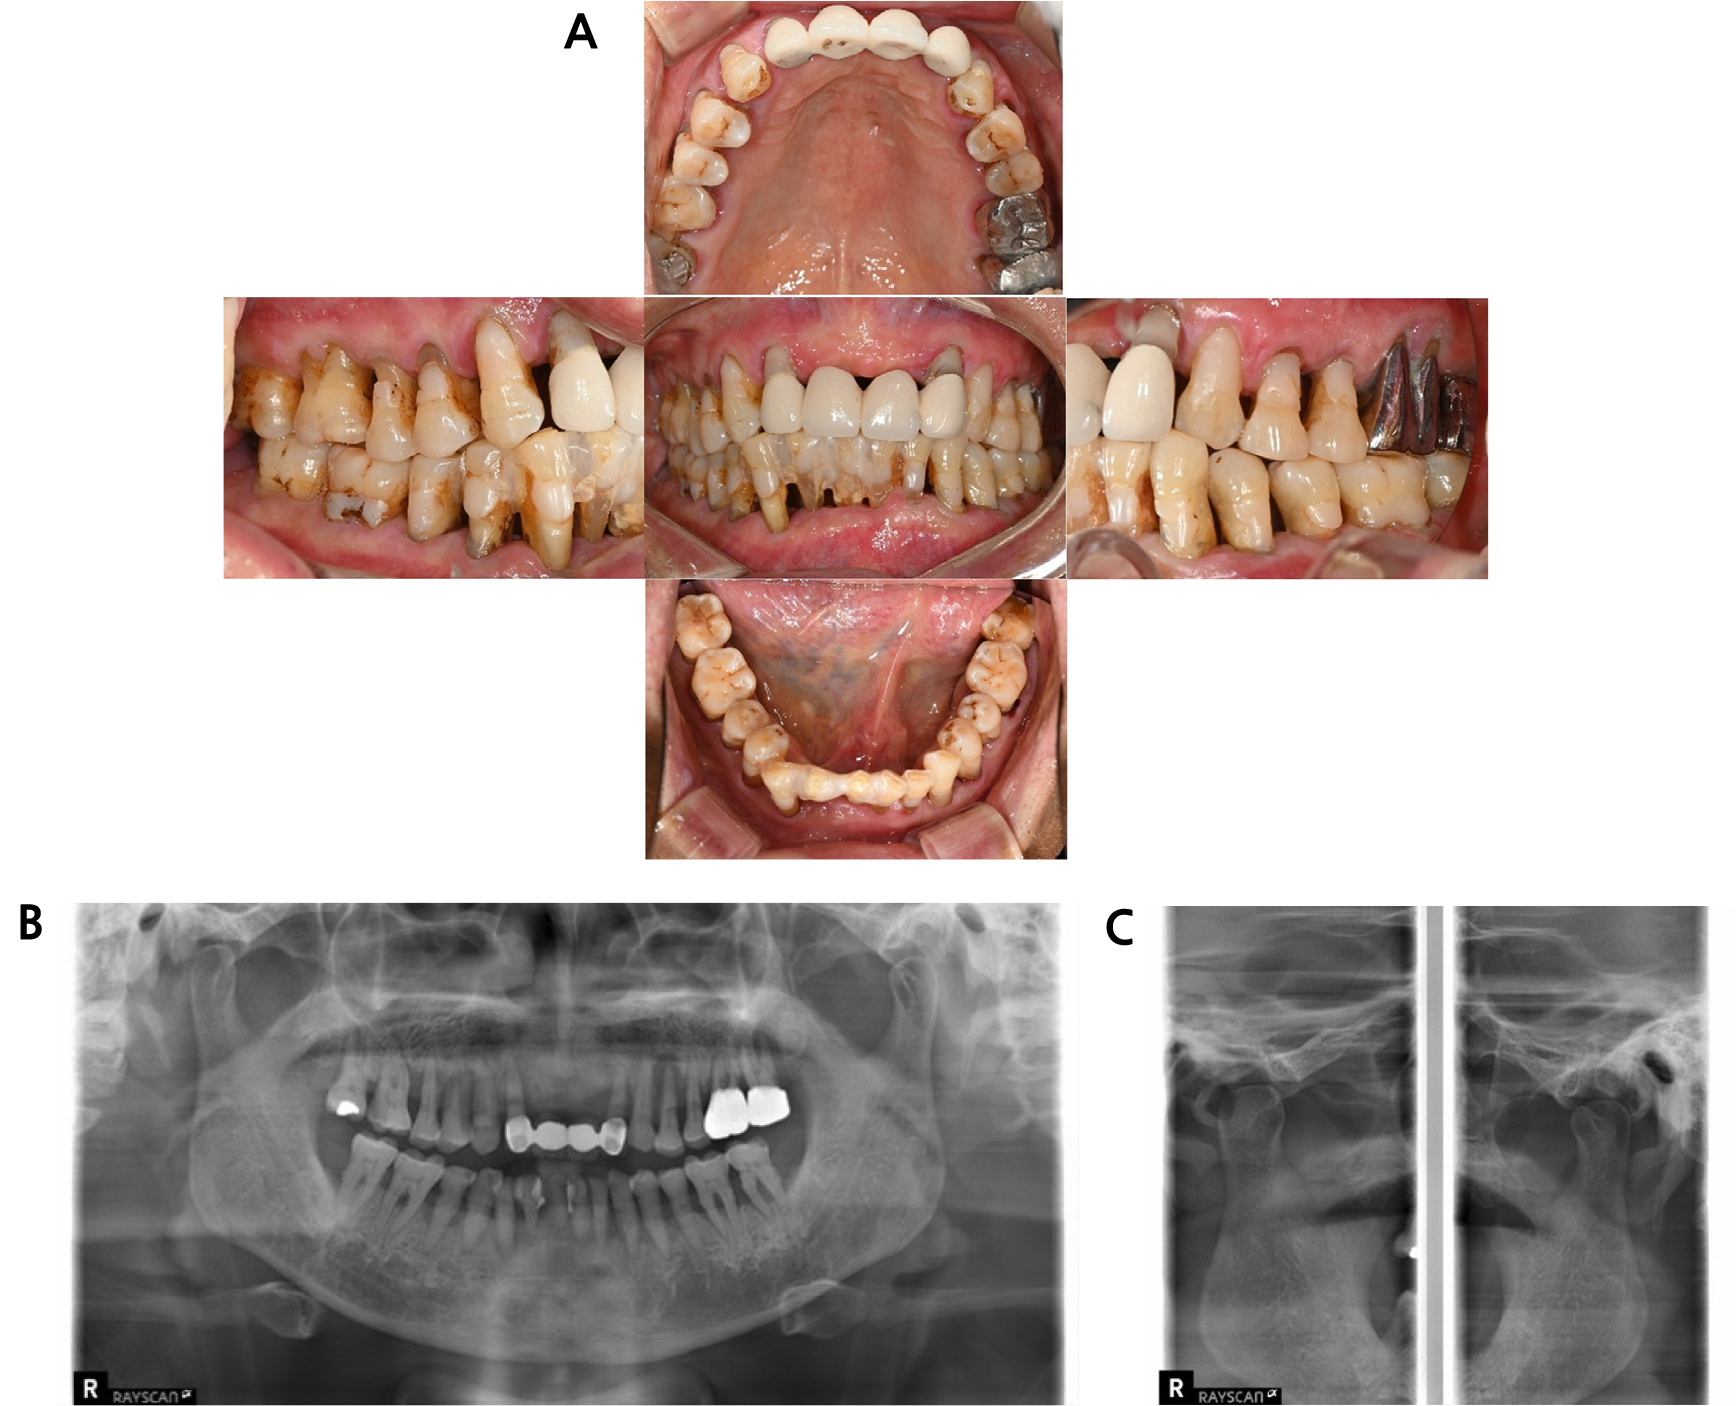

An 80-year-old male patient presented with difficulty eating due to generalized tooth mobility. His medical history included diabetes and a previous colectomy, but he was not taking any medications. Clinical and radiographic examinations revealed alveolar bone loss and Grade III mobility in all maxillary teeth except tooth 17. In the mandible, teeth 31, 32, 41, and 42 were in a hopeless condition with severe mobility, whereas teeth 34, 35, 36, 37, 44, 45, and 46 exhibited Grade II mobility, and tooth 47 showed Grade I mobility (Fig. 1). No specific abnormalities were observed in the temporomandibular joint upon radiographic evaluation.